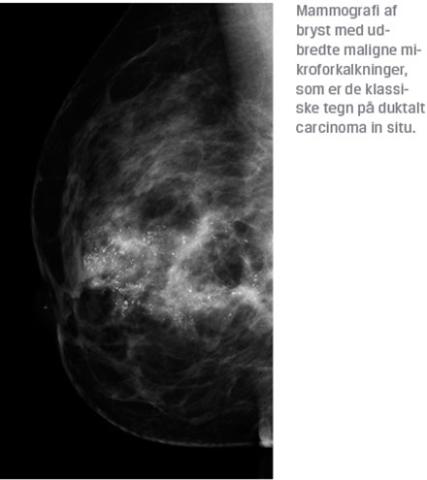

Før indførelsen af screening udgjorde DCIS ca. 5% af det samlede antal præmaligne og maligne tilstande i brystet, og kvinderne havde typisk en palpabel tumor eller patologisk sekretion fra papillen. DCIS er efter indførelse af screening oftest asymptomatisk og diagnosticeres som mikroforkalkninger på mammografi [8]. Diagnosen stilles histologisk på basis af grovnålsbiopsier, der ofte foretages mammografivejledt (stereotaktisk). I nogle tilfælde kan kirurgisk excisionsbiopsi være nødvendig for at stille diagnosen. Forud for operationen markeres det billeddiagnostisk suspekte område på røntgenafdelingen.